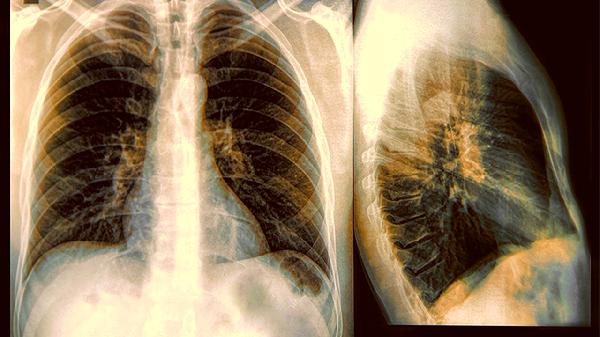

40岁以上人群建议每年做低剂量CT检查,尤其是吸烟者。胸片检查对早期病变的检出率有限,容易漏诊。